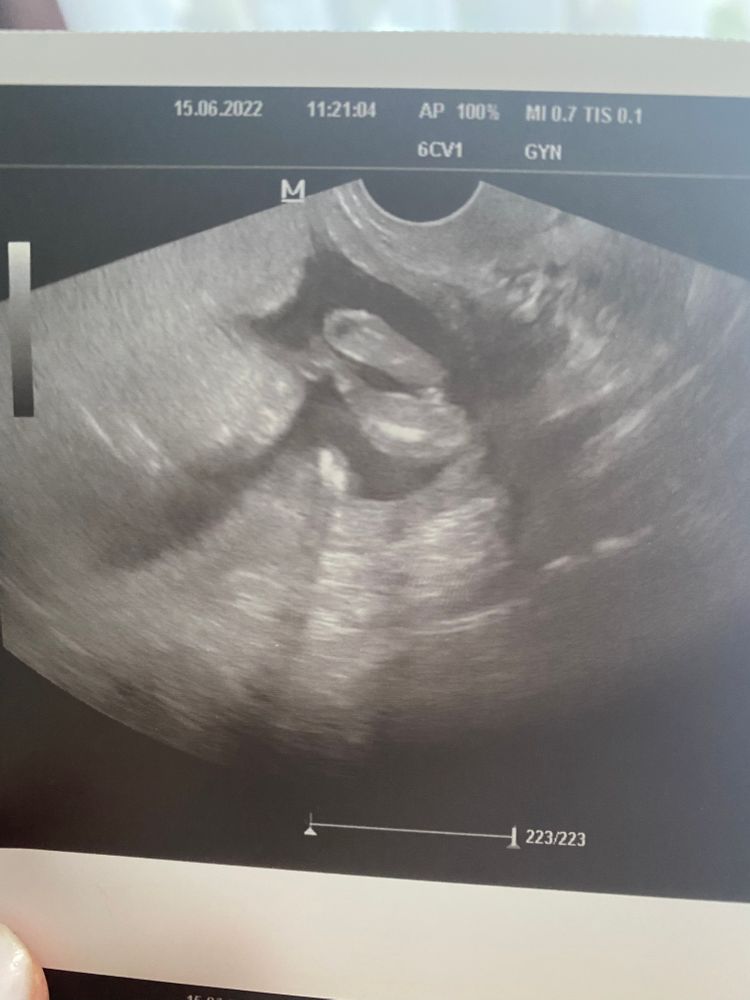

Делаем ставки: кто?

Я думаю, мальчик

Мальчик

Соглашусь с врачом, мне видно мошонку и кончик писюна))

100% мальчик👶у нас такое же фото,и стручёчек видно😄

Вижу мальчика)

А я думаю девочка 💕👌🙂

Я думаю, что мальчик)

Мальчик 99%)

Ракурс неудачный(

abcwish, ну, какой поймали. Кроха неугомонная, балованная. Крутился